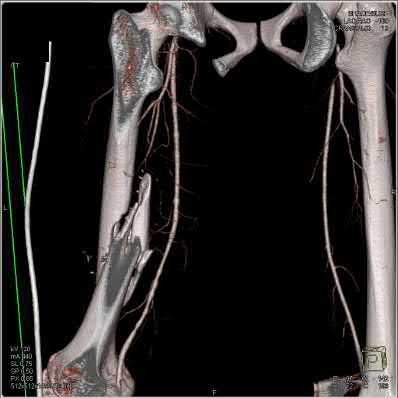

Question 19

A 28-year-old male sustains a closed comminuted tibial shaft fracture.

Two hours post-injury, he develops severe leg pain unyielding to narcotics. His blood pressure is 120/80 mmHg. Intracompartmental pressure monitoring is performed. Based on current guidelines, which measurement dictates an emergent 4-compartment fasciotomy?

Explanation

Acute compartment syndrome is classically defined by tissue hypoperfusion. The absolute compartment pressure is less reliable than the differential pressure (Delta P). A Delta P (Diastolic Blood Pressure minus Compartment Pressure) of less than 30 mmHg is an absolute indication for emergency fasciotomy, as capillary perfusion gradient is lost when tissue pressure approaches the diastolic pressure.